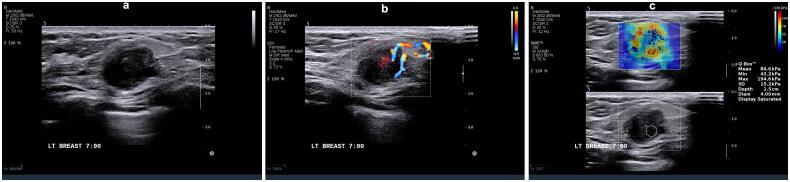

We performed a retrospective analysis encompassing 310 young women with breast cancer. Observations were made regarding the ultrasonography and elastography characteristics of the identified breast lesions. Subsequently, based on immunohistochemistry results patients were classified into five distinct molecular subtypes: luminal A, luminal B (HER2-), luminal B (HER2+), HER2+, and triple-negative breast cancer (TNBC). Clinical, pathological, and ultrasound imaging features were compared among these subtypes using binary logistic regression analysis.

Statistically significant differences were observed in various parameters across the five molecular subtypes ( < 0.05), including tumor size, morphology, margins, calcification, posterior echo features, blood flow (Adler grading), and tumor hardness. Specifically, luminal A subtype exhibited propensity for spiculated margins, lower blood flow grading, and decreased hardness; luminal B subtype was characterized by angular margins; HER2+ subtype manifested higher blood flow grading, calcification, and elevated hardness. Conversely, TNBC subtype displayed smooth margins, absence of calcification, and heightened hardness.

Specific molecular subtypes of breast cancer have unique ultrasonic and elastic imaging characteristics.